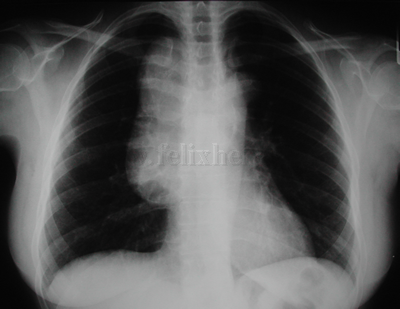

Timoma |